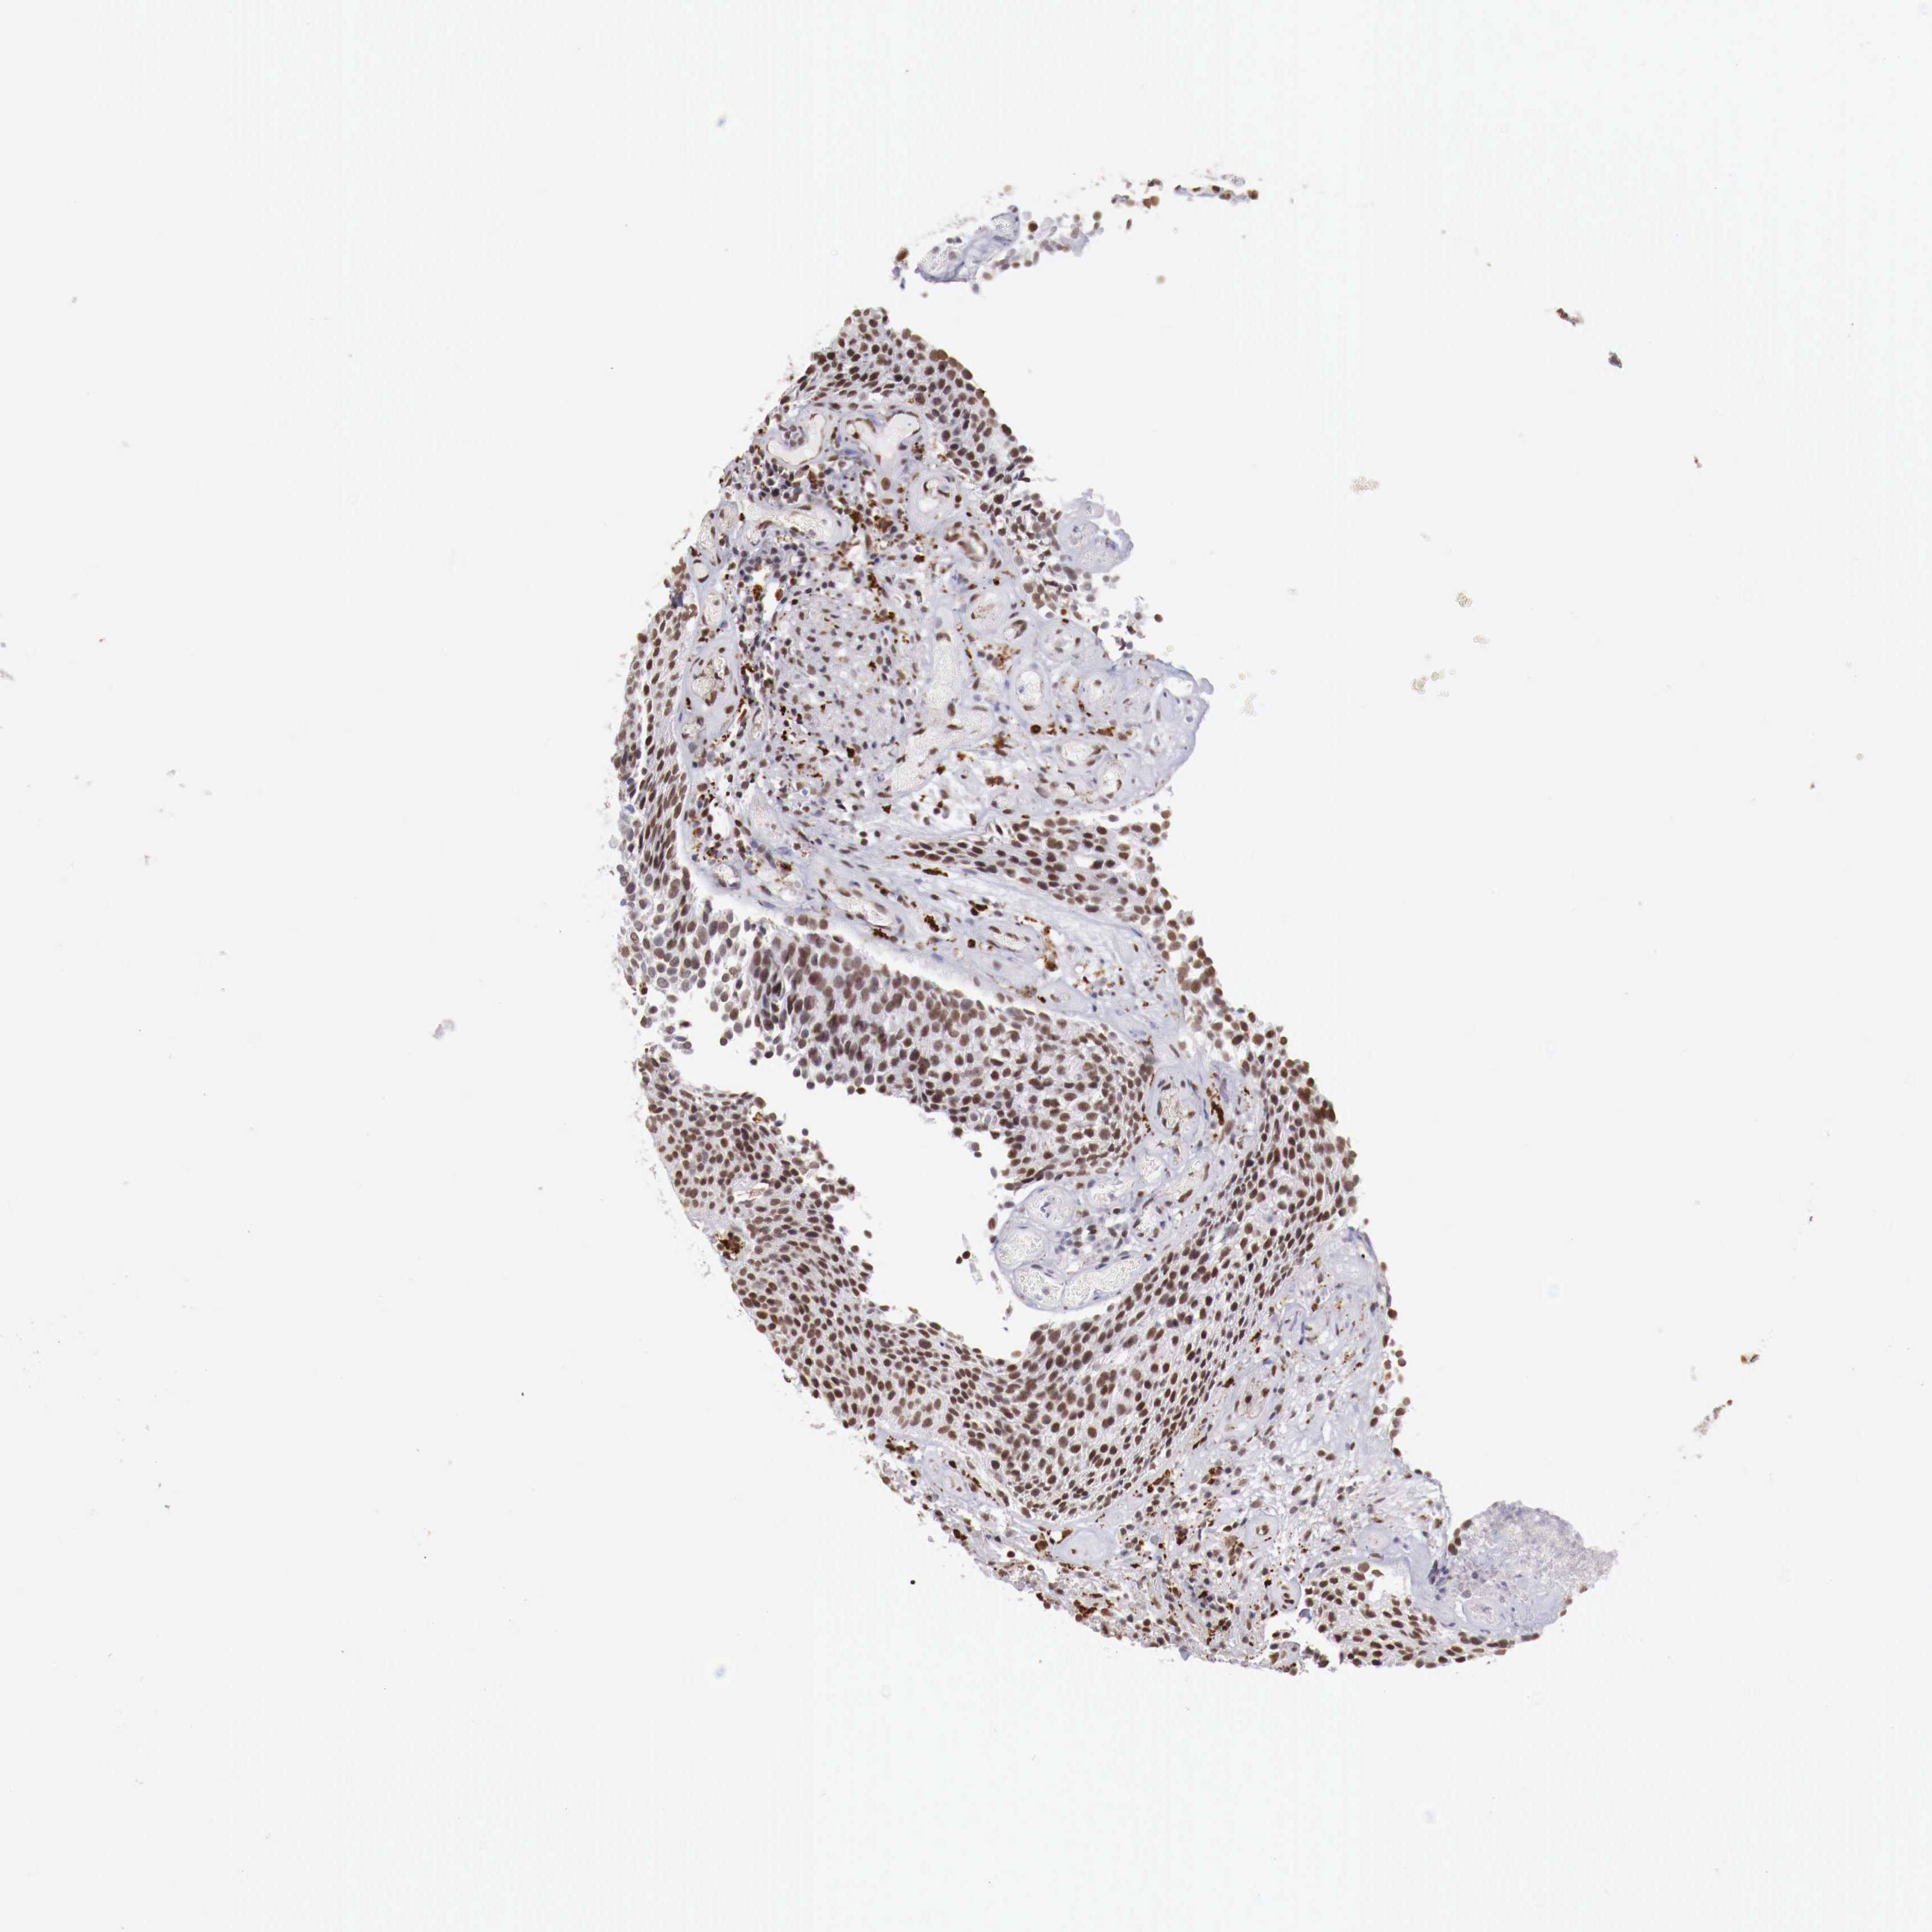

UROTHELIAL CANCER - Protein expressioni

A mouse-over function shows sample information and annotation data. Click on an image to view it in a full screen mode. Samples can be filtered based on level of antibody staining by selecting one or several of the following categories: high, medium, low and not detected. The assay and annotation is described here.

Antibody stainingi

Antibody staining in the annotated cell types in the current human tissue is reported as not detected, low, medium, or high, based on conventional immunohistochemistry profiling in selected tissues. This score is based on the combination of the staining intensity and fraction of stained cells.

Each image is clickable and will lead to virtual microscopy that enables deeper exploration of all samples and also displays staining intensity scores, fraction scores and subcellular localization as well as patient and tissue information for each sample.

Antibody CAB000328

Urothelial carcinoma, Low grade